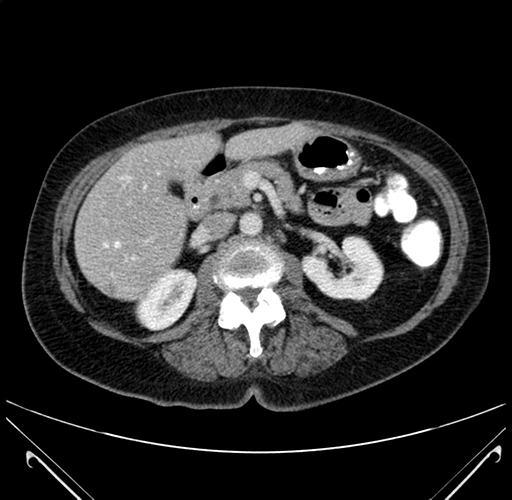

Pre-Chemo: Axial Venous

Axial Venous